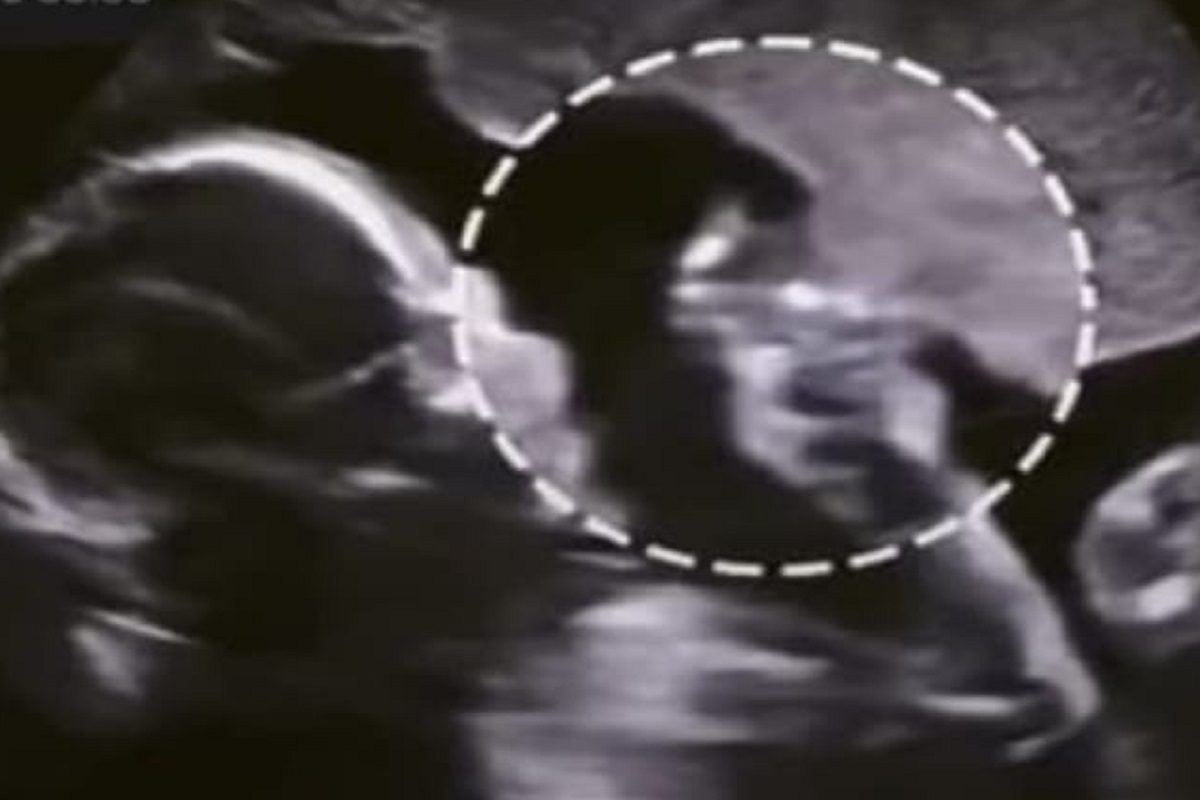

नवी दिल्ली, 29 जून : आईच्या पोटात असलेलं बाळ लाथा मारताना तुम्ही पाहिलं असेल. लाथा मारताना बाळाची पावलं पोटावरही स्पष्टपणे दिसतात. पण आता एक असं बाळ जे आईच्या पोटात लाथा मारण्याव्यतिरिक्त असं काही करताना दिसलं, की व्हायरल व्हिडीओ पाहून सर्वजण थक्क झाले आहे. बाळाचं आईच्या पोटातील ते कृत्य अल्ट्रासाऊंडन मशीनमध्ये कैद झालं आहे. बाळाचं सर्वात पहिलं नातं जुळतं ते त्याच्या आईच्या. गर्भापासूनच या नात्याची सुरुवात होते. आईचं खाणंपिणं, तिचं वागणं या सर्वांचा परिणाम त्या बाळावर होत असतो. आईच्या पोटात बाळ काय करत असेल, असा प्रश्न अनेकांना पडतो. अल्ट्रासाऊंडमध्ये पोटातील बाळाला आपल्याला पाहता येतं, अशाच अल्ट्रासाऊंडचा हा व्हिडीओ आहे. ज्यात बाळ विचित्र काहीतरी करताना दिसलं.

माहितीनुसार ज्या बाळाचा हा व्हिडीओ आहे, तेव्हा हे बाळ पोटात पंधरा आठवड्यांचं होतं. म्हणजे चार महिन्यांना एक आठवडा कमी. इतक्या कमी दिवसांचं बाळ आईच्या पोटात असं काही करताना दिसलं की तुम्ही त्याचा विचारही केला नसेल. संतापजनक VIDEO! बाळाला उकळत्या दुधाची अंघोळ; तडफडत होता चिमुकला, सर्व पाहत राहिले तमाशा व्हिडीओत तुम्ही पाहू शकता बाळाने आपल्या हाताचा एक बोट उचललं आहे आणि ते बोट तो आईच्या पोटावर मारताना दिसतो आहे. जणू आईला तो खाजवतो आहे किंवा गुदगुदल्या करतो आहे, असंच पाहताच क्षणी वाटतं. @netflixnmovies इन्स्टाग्राम अकाऊंटवर हा व्हिडीओ पोस्ट करण्यात आला आहे. त्यावर बऱ्याच कमेंट येत आहेत. सुरुवातीला यावर कुणाचा विश्वासच बसत नव्हता. Shocking! नवजात बाळाला आले 3 Heart attack; नागपुरातील धक्कादायक प्रकरण, डॉक्टरांनी सांगितलं कारण काहींना हा व्हिडीओ मजेशीर वाटला. हे बाळ गर्भात असताना अशी स्थिती आहे तर बाहेर आल्यावर काय होईल, असं एका युझरने म्हटलं आहे. तर काहींनी बाळ पोटात असताना आईला किती त्रास सहन करावा लागतो, आई होण्याचा प्रवास खूप कठीण आहे, अशा कमेंटही केल्या आहेत.